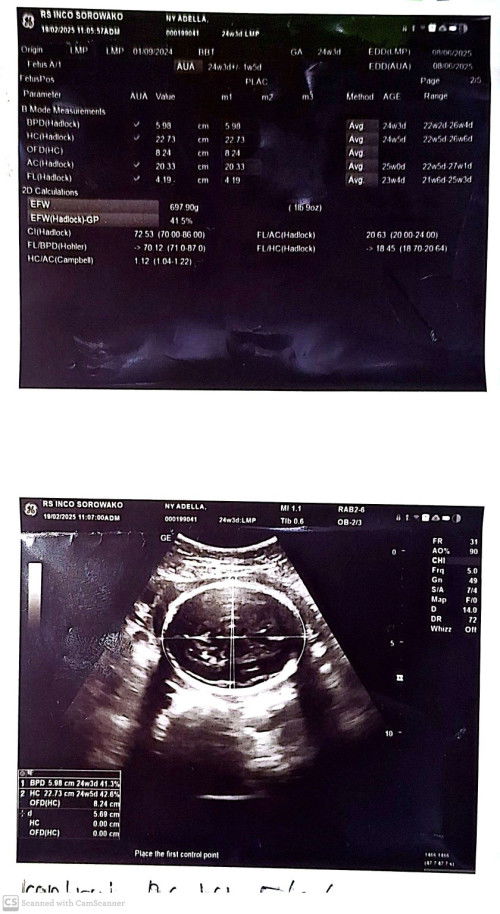

USG PERTAMA

Pertama kali melakukan USG pada usia kehamilan 24 minggu!#sharing